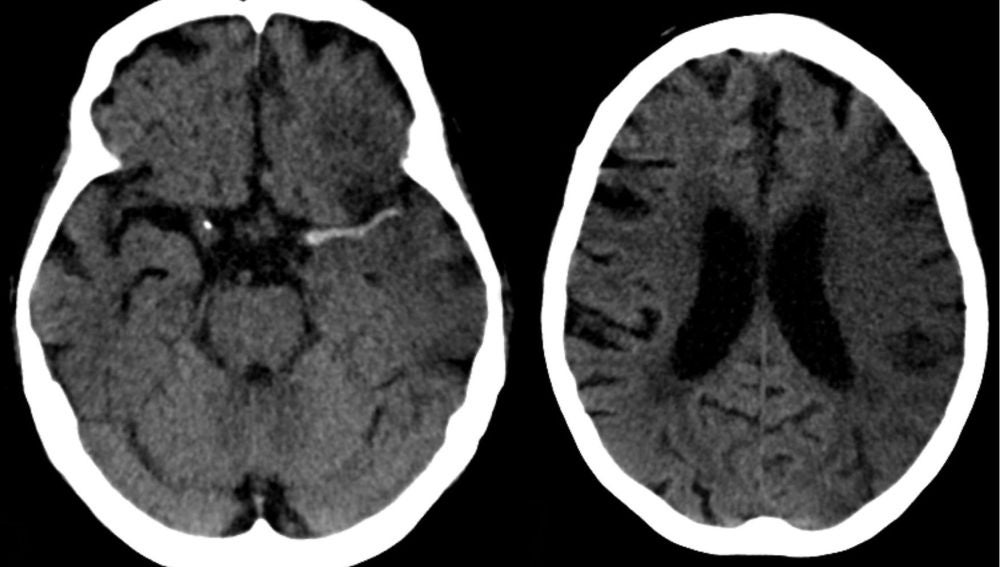

Ictus en arteria cerebral media (izda) y evolución a las 7 horas (dcha). wikipedia